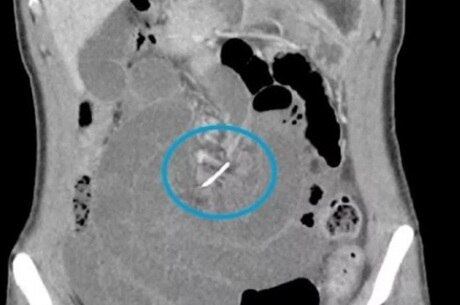

Finalmente, após realizar uma tomografia computadorizada, os médicos descobriram que havia um fio metálico cutucando o intestino da mulher. Segundo a Dr. Talia Shepherd, que cuidou do caso, o acontecimento não é comum.

Exame tomografia que havia um fio cutucando o estômago da mulher